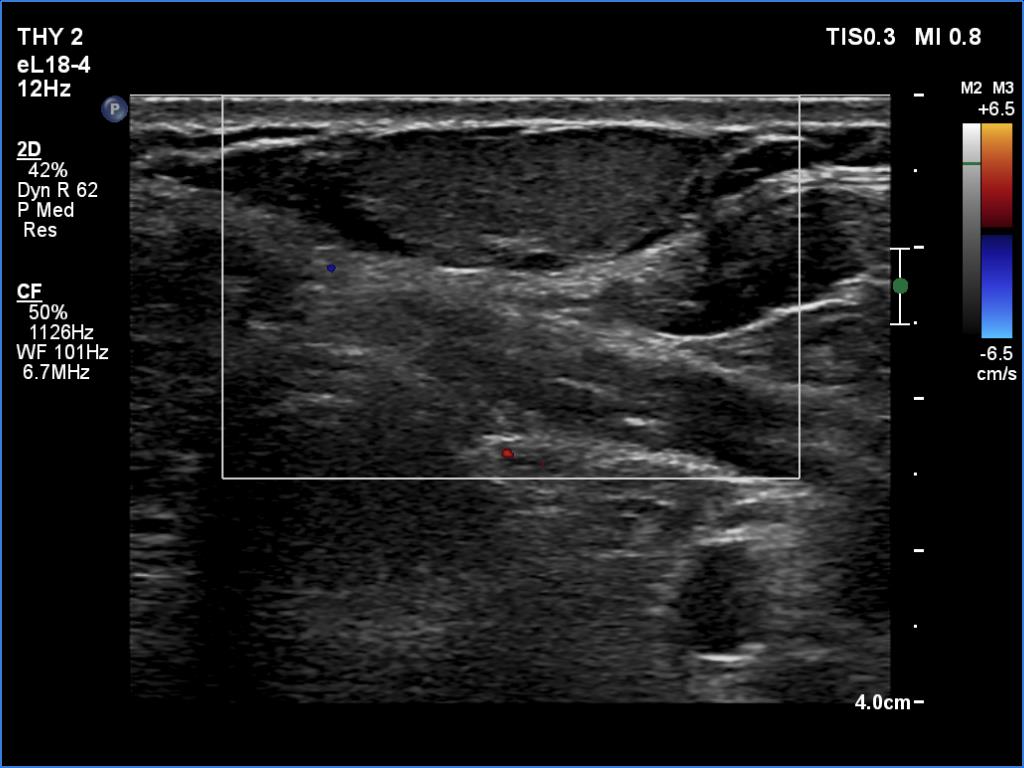

Ultrasonography. The thyroid was echonormal and had several small cystic lesions without any clinical or oncological importance. According to the palpable mass, a moderately hypoechoic lesion was detected several centimeters under the thyroid in the middle of the neck. The lesion was within the muscle tissue. It was homogeneous and presented no vascularity.

Aspiration cytology of the lesion resulted in lipoma.